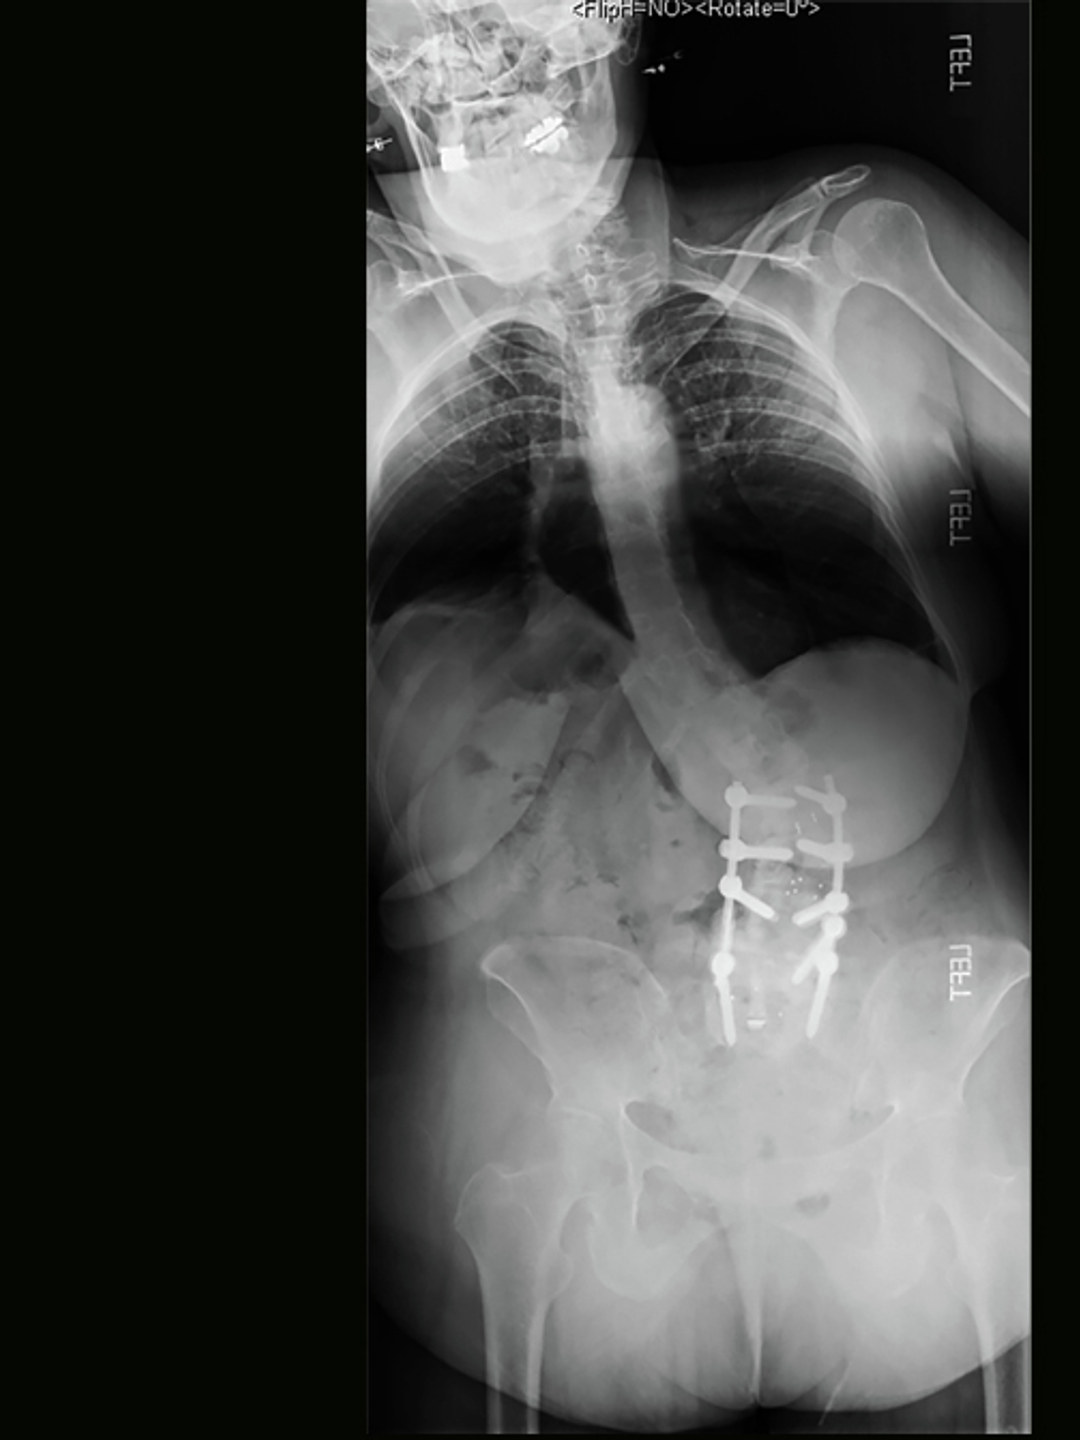

An X-ray shows a woman with a severe curvature of the spine and lower back fusion screws

Figure 1: Kyphosis, kyphoscoliosis, and nonunion in a 59 y.o. patient following L3-5 laminectomy and fusion at an OSH.

Mrs. T, a 59-year-old woman, was referred to the Penn Spine Center to correct a series of complications resulting from four previous lumbar operations. These complications include heterotopic ossification, dense fibrous scarring, osteoporosis, L2 proximal junctional kyphosis and kyphoscoliosis, and nonunion following a previous L3-5 laminectomy and fusion (Figure 1). At presentation, she was in severe pain and wheelchair-bound.